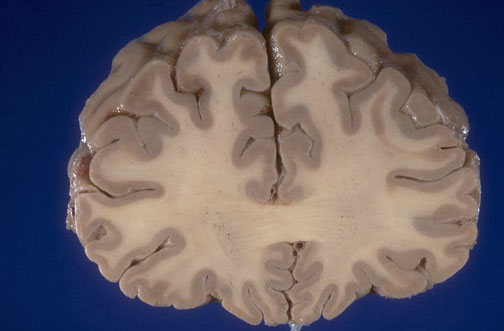

Identify the following regions of the normal brain, viewed here looking anterior to posterior, by clicking in the image below:

Right superior frontal gyrus - Right middle frontal gyrus - Right inferior frontal gyrus - Genu of corpus callosum